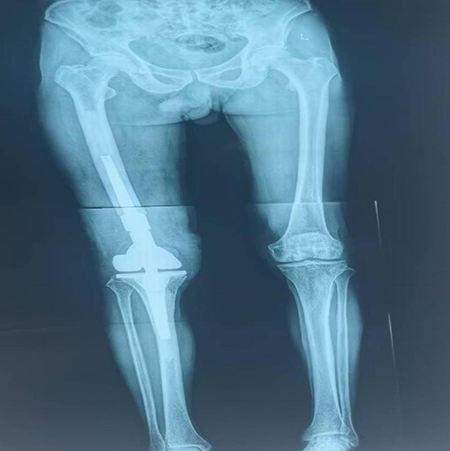

术后双下肢全长片